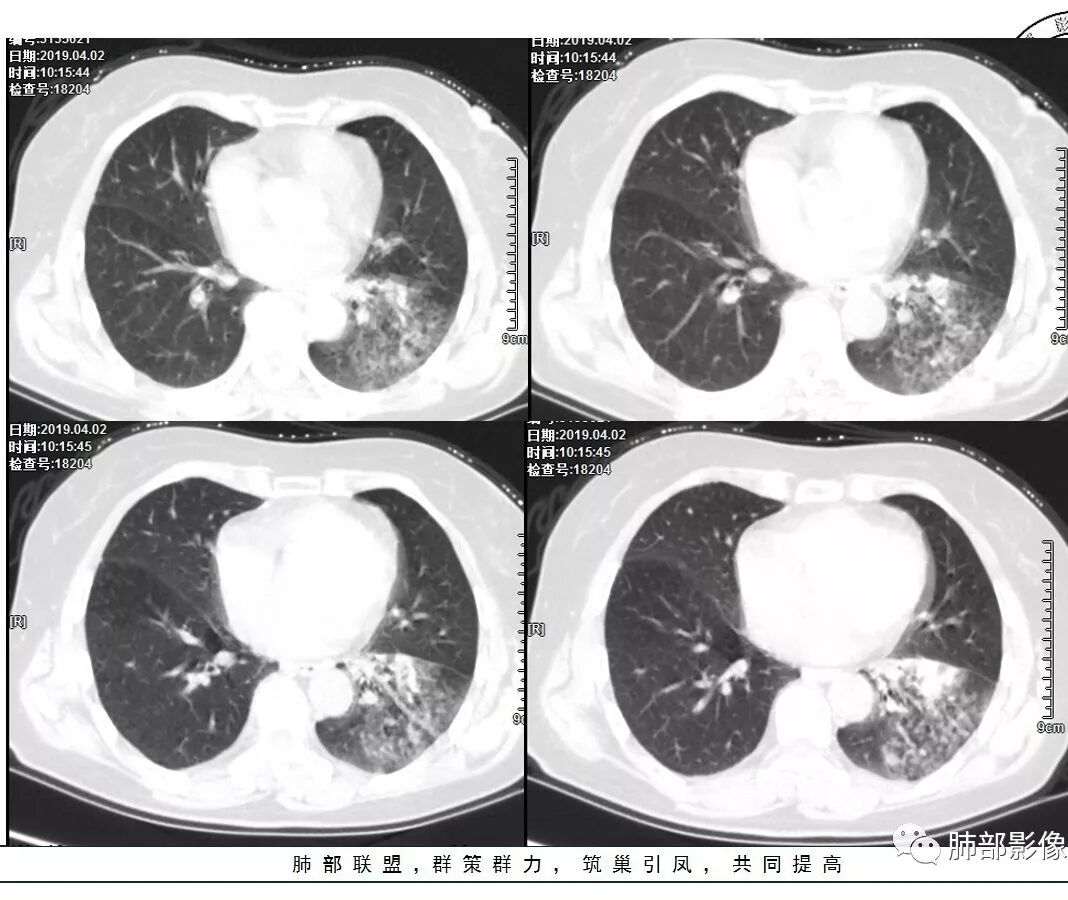

2.左肺下叶片状影及多数有边界的结节影,较散,多形性,密度不均(注意许多老师提到这个特点还是比较明显的)。左肺下叶体积未见缩小。

3.病灶强化比较明显。

4.左下叶支气管壁增厚,管腔不均匀狭窄,没有堵塞

5.肺门纵隔见增大钙化淋巴结。提示曾经存在慢性病损可能。

1.前述特点除强化外都还是很容易让人首先想到肺结核的可能性。结核是常见病。注意肉芽肿明显的结核灶可以观察到强化。

2.淀粉样变性病变支气管改变一般会更广泛,较少出现单叶肺的如此大片影。

3.腺癌不大会出现较散的腺泡样结节影,更不会出现如本例的支气管改变。增大钙化的淋巴结也很难相互关联。

4.相关支气管未见腔内结节及阻塞,女性患者,鳞癌的可能性更小。